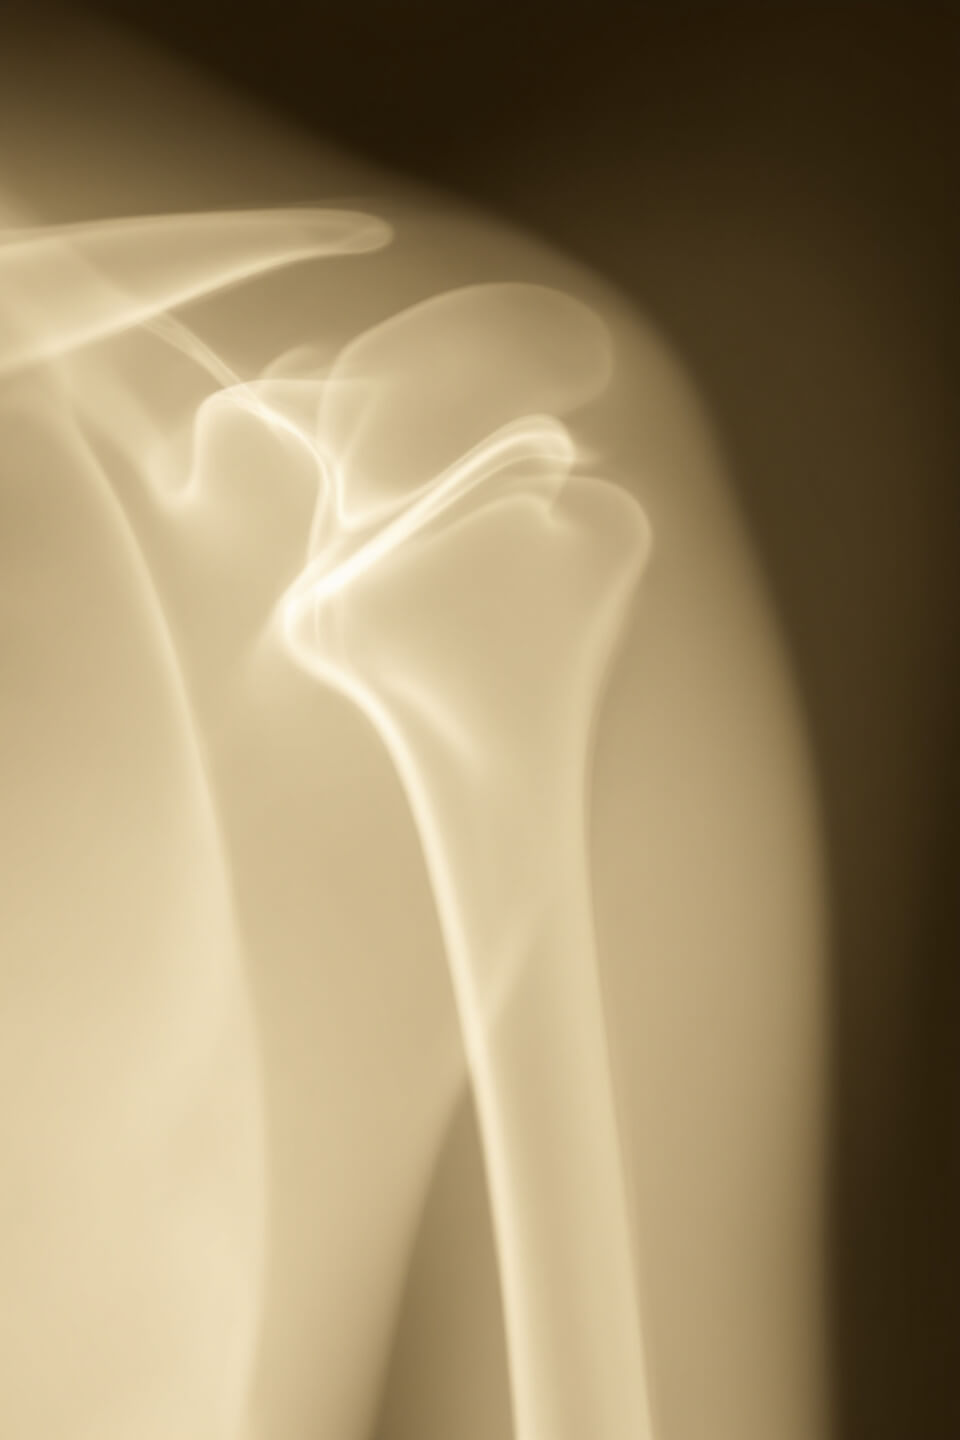

영상 검사

- X-ray: 골절이나 관절염을 확인합니다.

- MRI: 연조직(힘줄, 근육)의 상태를 평가합니다.

- 초음파: 힘줄 염증이나 손상을 확인합니다.